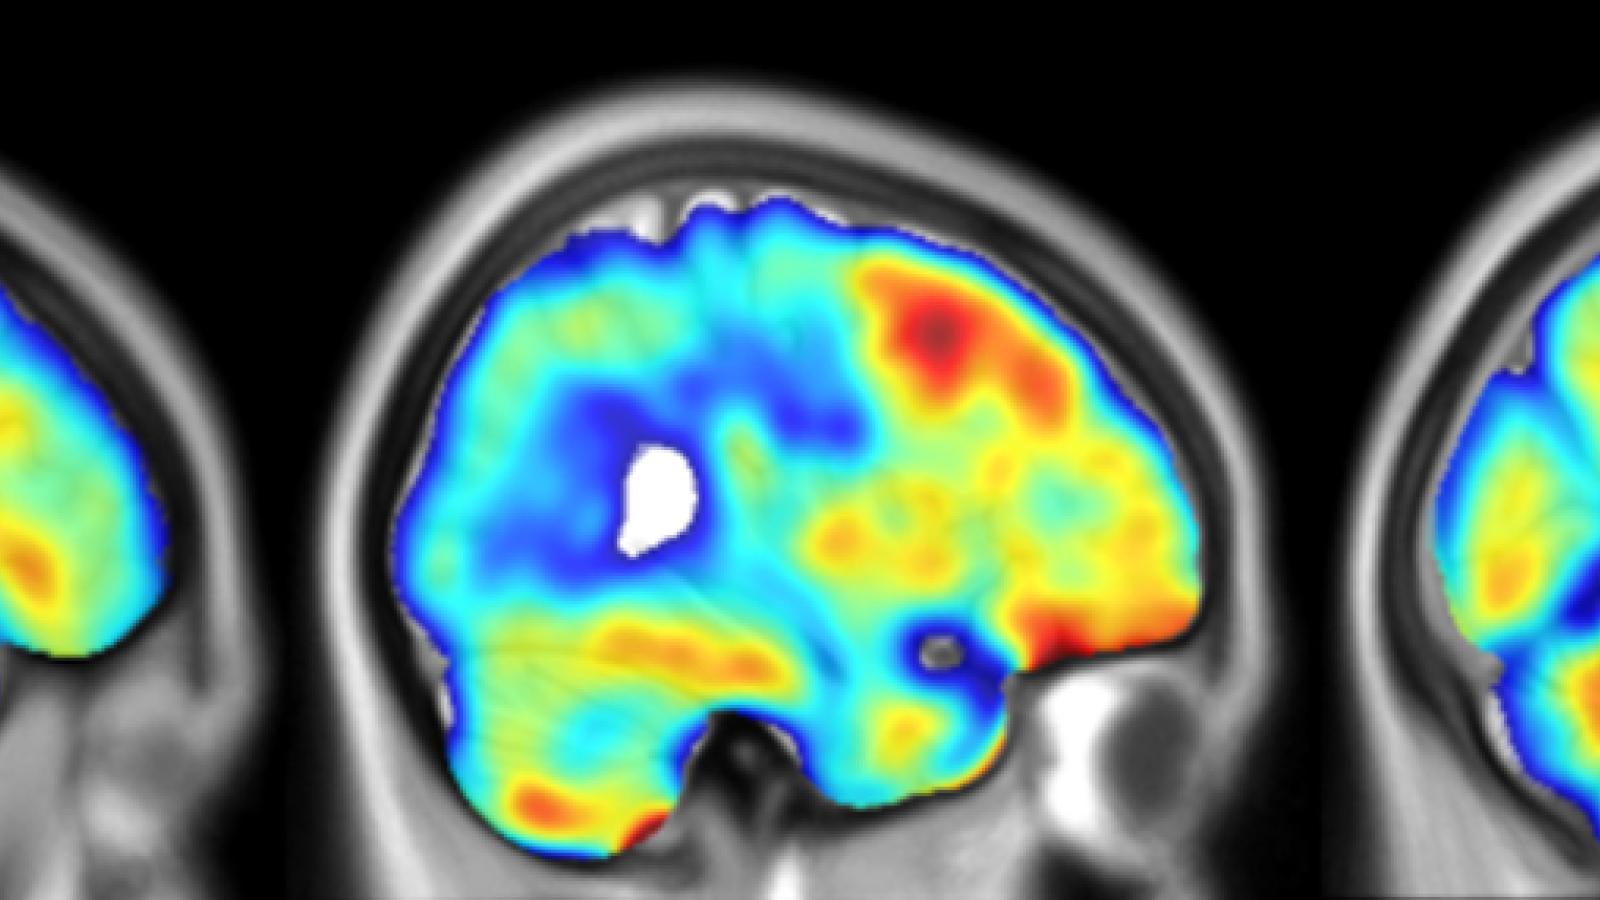

Three brains with dementia imaged with PET-TSPO

To study inflammation in the living brain, researchers use a type of brain scan called PET imaging. This scan uses special dyes, called radiotracers, that are injected in the blood of participants and attach to a protein called TSPO, which becomes more active when there is inflammation in the brain. Different research centres have developed various TSPO radiotracers, but their results are not always easily comparable. In this study, the team looked at how to make results from different TSPO tracers more consistent and comparable across research centres.